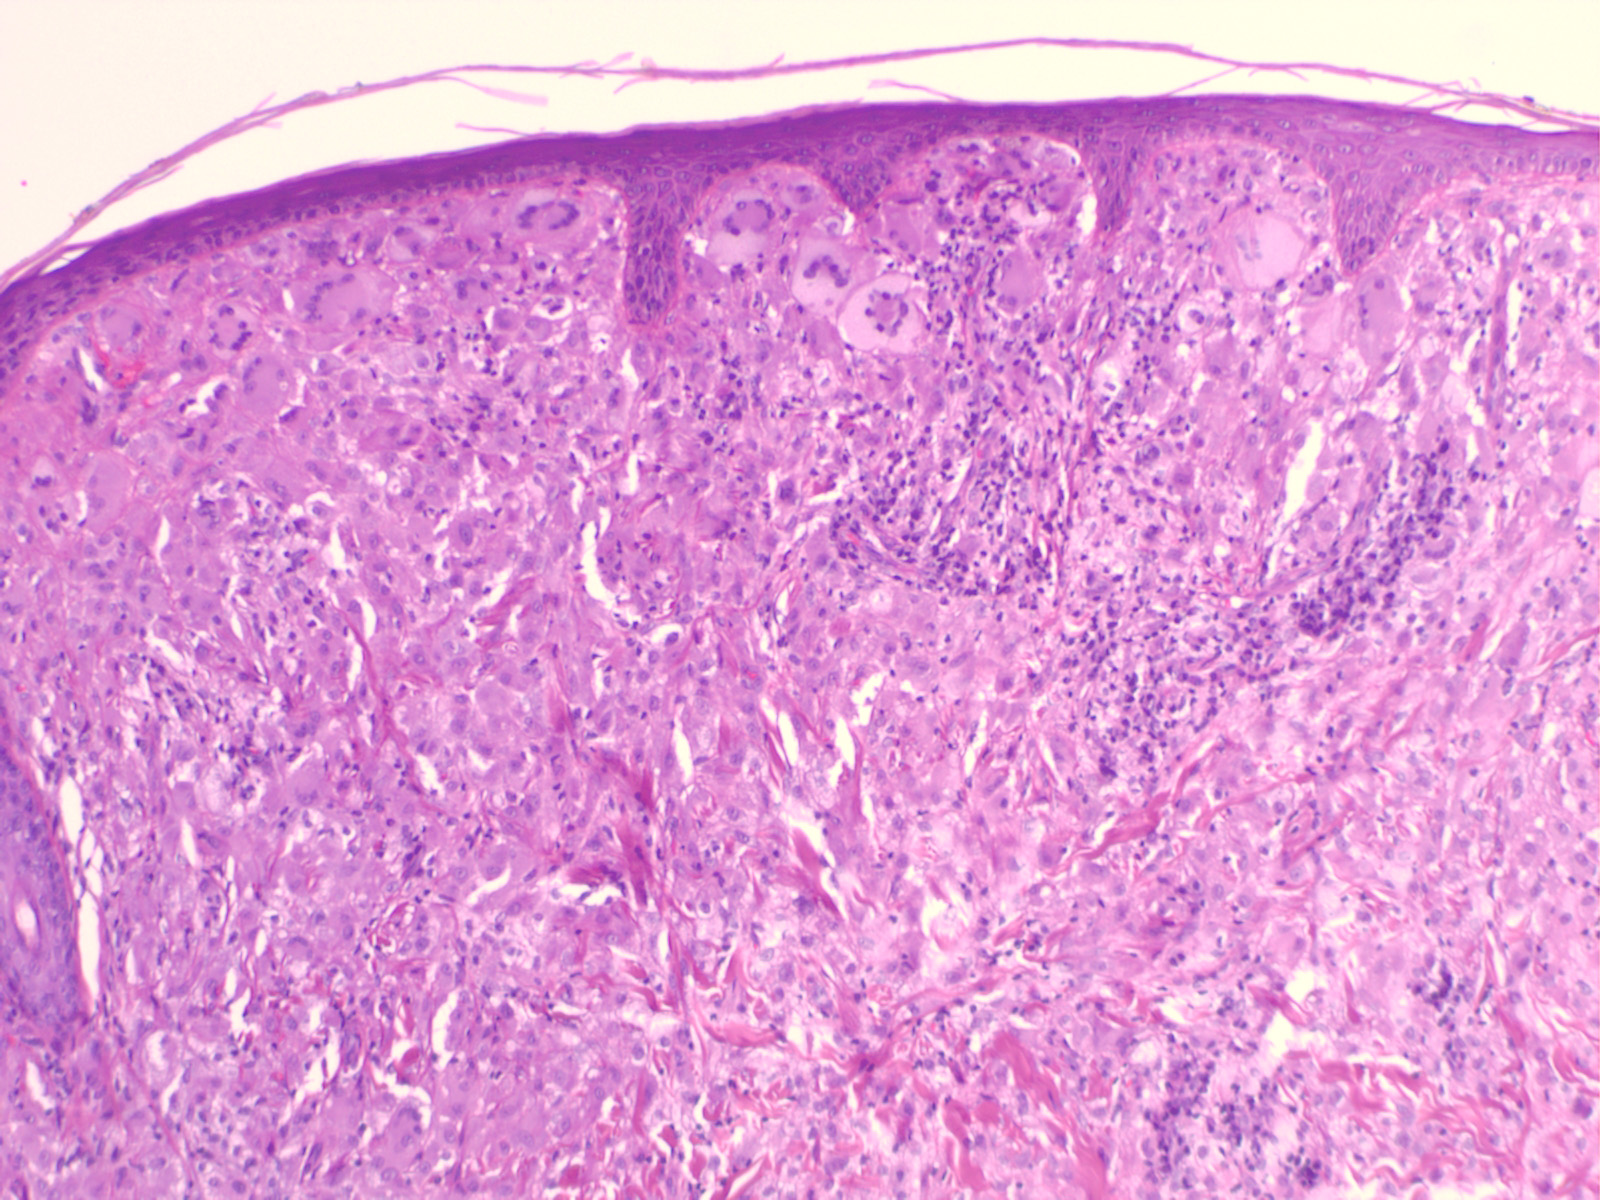

Biopsy sections of JXG lesions show a feature that is common to many NLCHs, that is, a nonepidermotropic histiocytic infiltrate lacking Langerhans granules. Early lesions of JXG are characterized by a monomorphous, non-lipid-containing histiocytic infiltrate that occupies at least the upper half, and sometimes the entire thickness, of the dermis. Mature lesions

contain foam cells, foreign-body giant cells, and Touton giant cells, mainly distributed in the superficial dermis and on the border of the infiltrate. Lymphocytes, eosinophils, and neutrophils are variably associated. Older lesions may show fibrosis. In mature lesions, fat stains yield positive results. The majority of JXG lesional biopsy sections stain positive for CD68/Ki-M1P and factor XIIIa but negative for CD1a and S100 protein.

Under the electron microscope, the histiocytes that characterize the early stage of the disease exhibit pleomorphic nuclei, are rich in pseudopods, and contain many elongated and irregular dense bodies. Clusters of comma-shaped bodies can occasionally be observed. In older lesions, there is a predominance of foam cells, the cytoplasm of which is completely filled with lipid vacuoles, cholesterol clefts, and myeloid bodies. Touton giant cells are extremely large and sometimes contain more than 10 nuclei. Lipid material fills the periphery, whereas mitochondria and lysosomes predominate at the center.